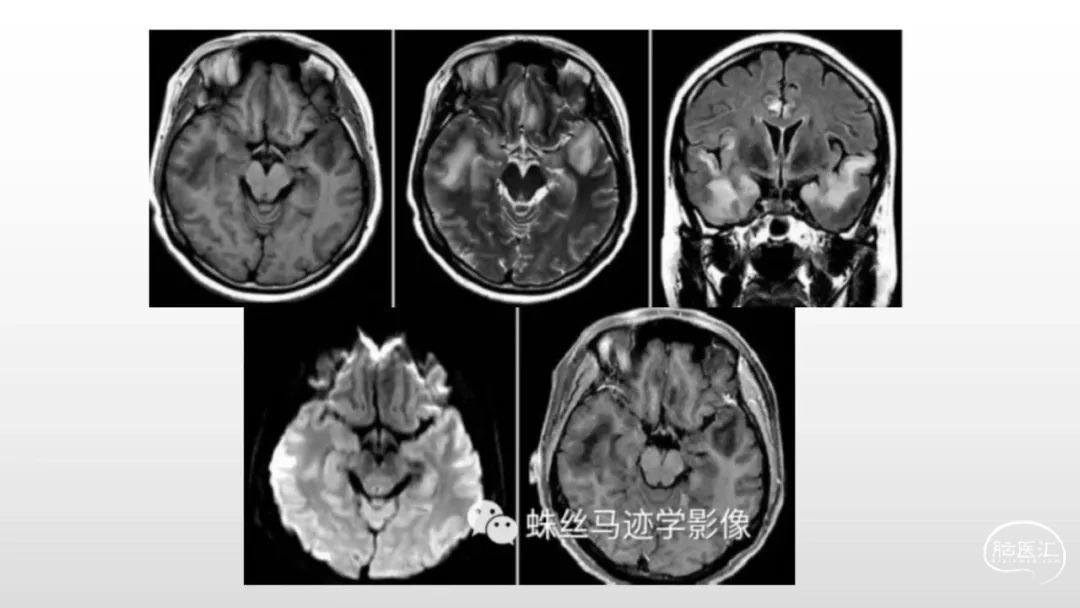

颅脑影像诊断基础知识讲座:感染和免疫性疾病2